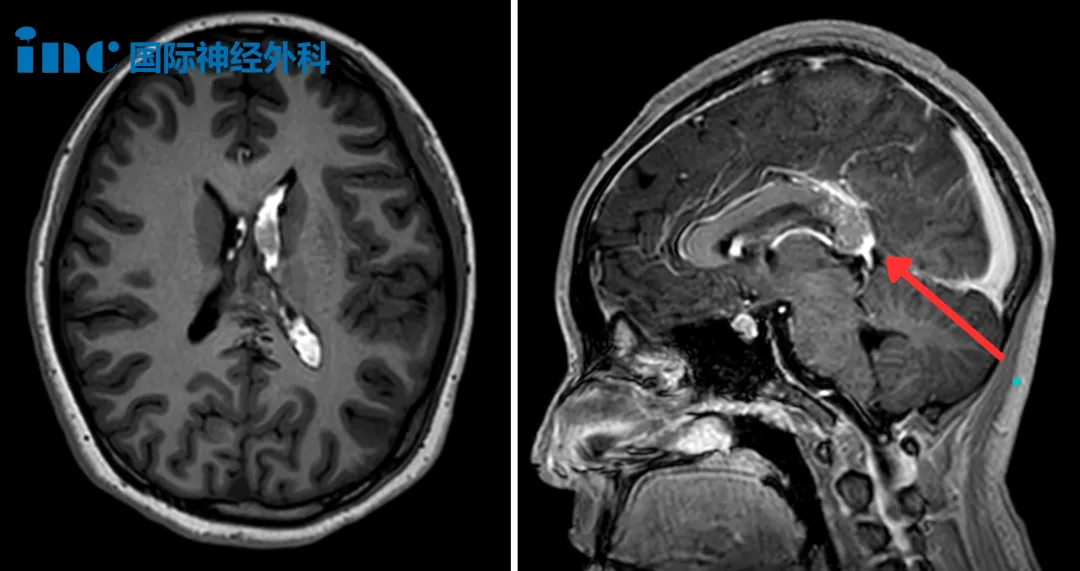

"切除率达到100%,动静脉畸形(AVM)无任何残留,我认为不会再复发。"2025年12月中旬,INC巴特朗菲教授在华进行示范手术期间,在详细审阅15岁患者小蕊术后6个月的最新MRI影像后,向家属宣布了这一令人安心的随访结论。

三天后,医生拔除了右侧引流管,保留左侧引流管继续引流脑脊液。当日进行的MRI检查揭示了更复杂的病情:胼胝体压部存在一个22mm×15mm的橄榄形动静脉畸形(AVM)。

术后第一天,小蕊即从ICU转入普通病房。术后MRI影像清晰显示:AVM已完全切除,脑室内出血也已清除。小蕊临床状况良好,很快恢复了正常活动能力。

在近期的术后半年随访中,巴教授特别指出:"通常情况下脑室内出血会引发脑水肿,但患儿恢复情况良好,未出现脑水肿。经过6个月时间,脑脊液循环已恢复正常。"